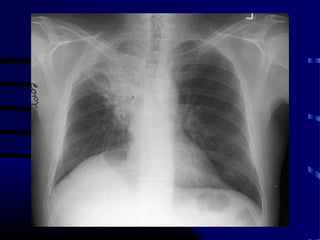

Question

• Patient is a 65 year old smoker with

following CXR and CT scan of chest:

• What test do we order next?